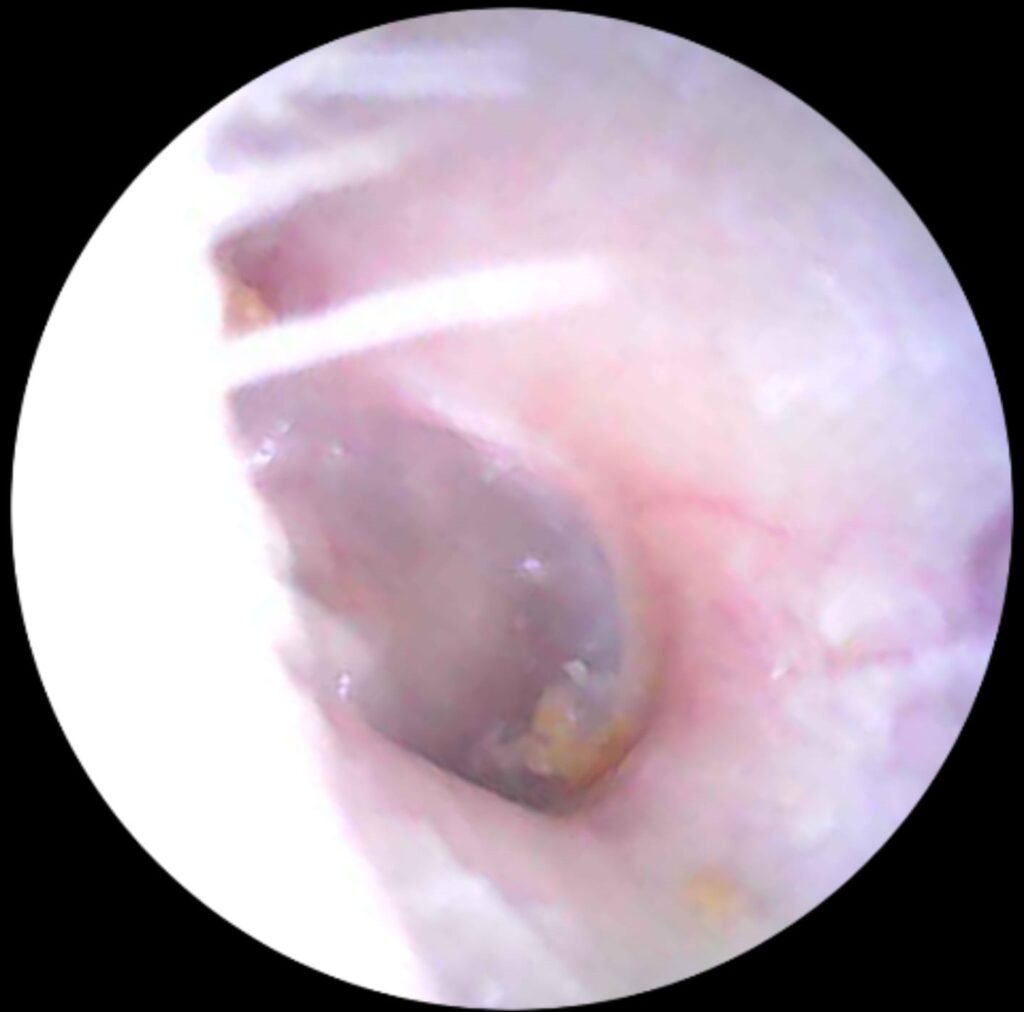

Do your ears feel “full,” muffled, or even a little itchy? You might be dealing with blocked ears; a common problem caused by earwax buildup. While it’s usually harmless, blocked ears can be uncomfortable, affect your hearing, and sometimes even cause ringing or dizziness. The good news? Professional earwax removal is safe, quick, and can make your ears feel like new again.

Why You Shouldn’t Try to Fix It Yourself

Blocked ears are more common than you think — but they don’t have to affect your daily life. Professional earwax removal can restore your hearing, comfort, and confidence.